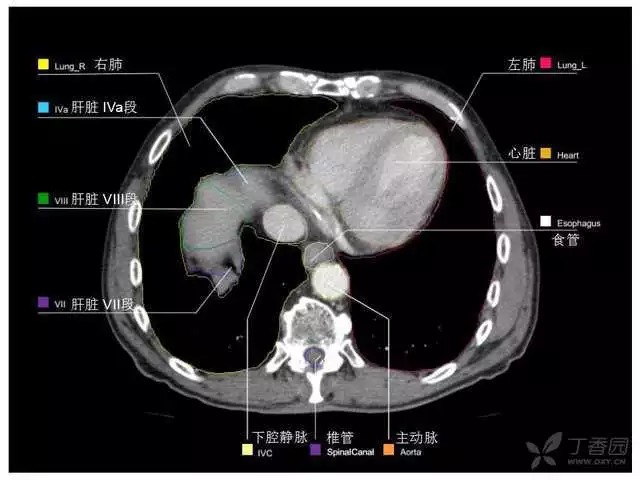

腹部肝脏高清CT断层的图谱

全腹部高清CT图谱,淋巴结彩色图谱,血管解剖图谱大汇总!

肝段,肝内管道的分布规律